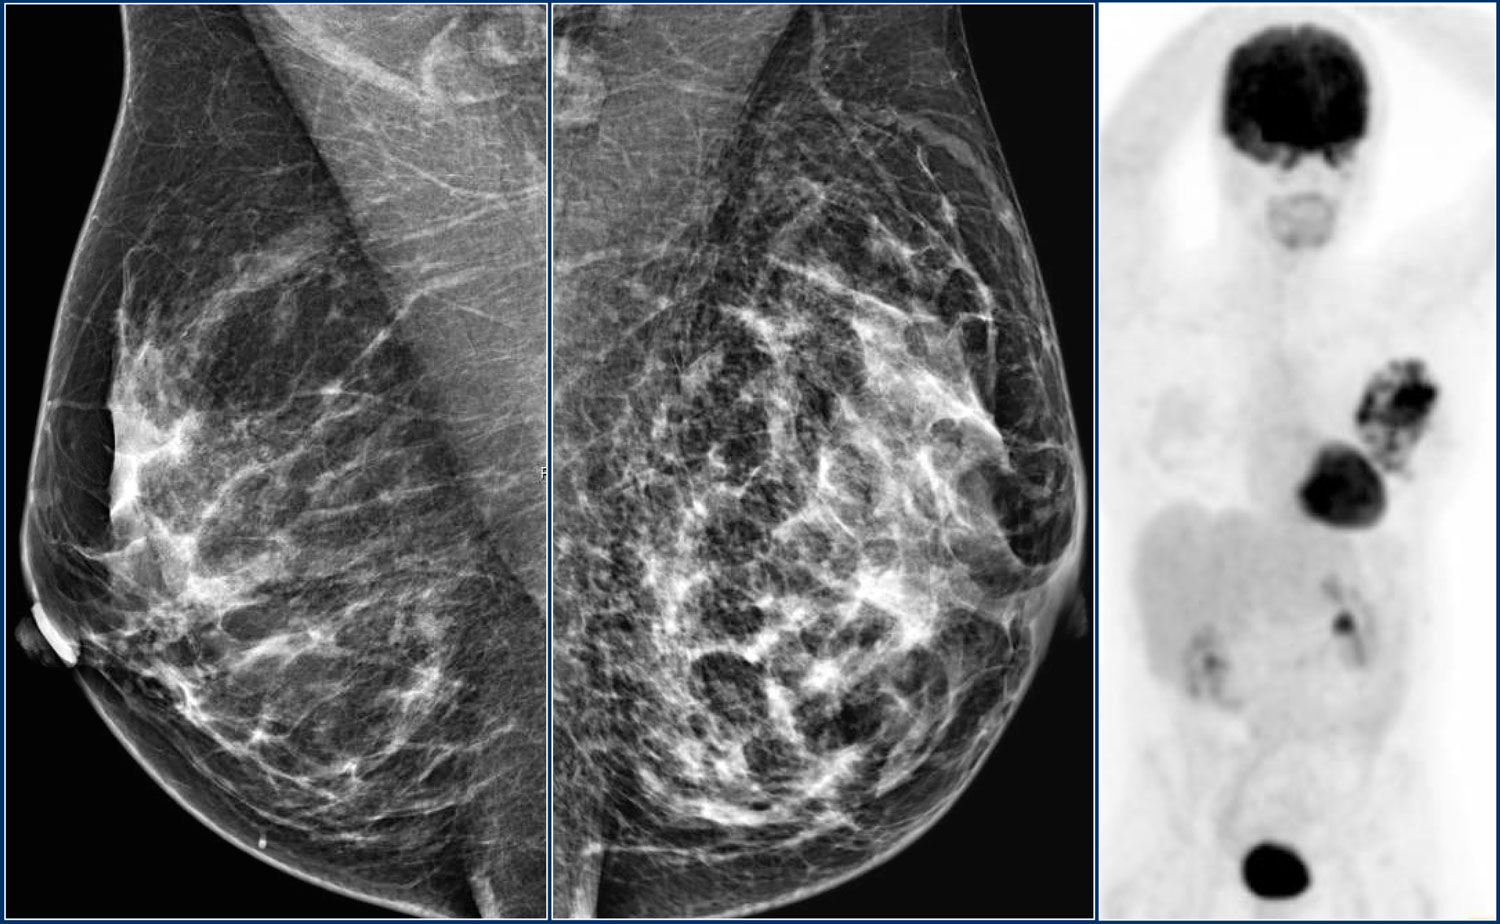

Фиброаденома молочной железы - доброкачественное образование, которое часто встречается у женщин. Оно может быть обнаружено при помощи различных методов диагностики, включая маммографию. Ниже представлены фотографии, помогающие понять, как выглядит данное заболевание.

Злокачественные опухоли молочных желез

Маммография и ее роль в диагностике фиброаденомы молочной железы

Маммография - это рентгенологическое исследование молочных желез. Оно позволяет выявить различные изменения в тканях, включая фиброаденому. На маммограммах можно увидеть структурные особенности опухоли и отследить ее динамику во времени.